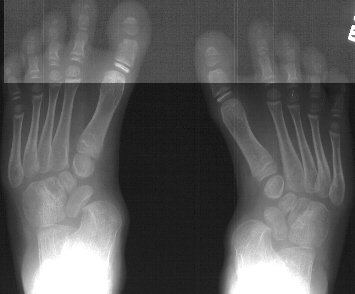

A 6 year old white male presents with a history of an undiagnosed

skeletal dysplasia. Previous surgery includes bilateral femoral

and tibial osteotomies for valgus deformities. His knee alignment

is now normal. His main complaint is the development of painful

callus over the arch of his foot and difficult in fitting shoes.

These deformities of the feet have been getting worse by the description

given by the mother. His foot deformity has never been treated

with casts or splints. On examination he has a short thick foot

with a kidney bean shaped curve to its lateral border. The arch

is not high but has a heavy callus bilaterally. The following

bilateral foot deformities were also present on physical examination:

hindfoot valgus of approx. 20-30 degrees, metatarsus adductus,

and prominence of the talar head in the medial arch with thickened

callus over the bony prominence.